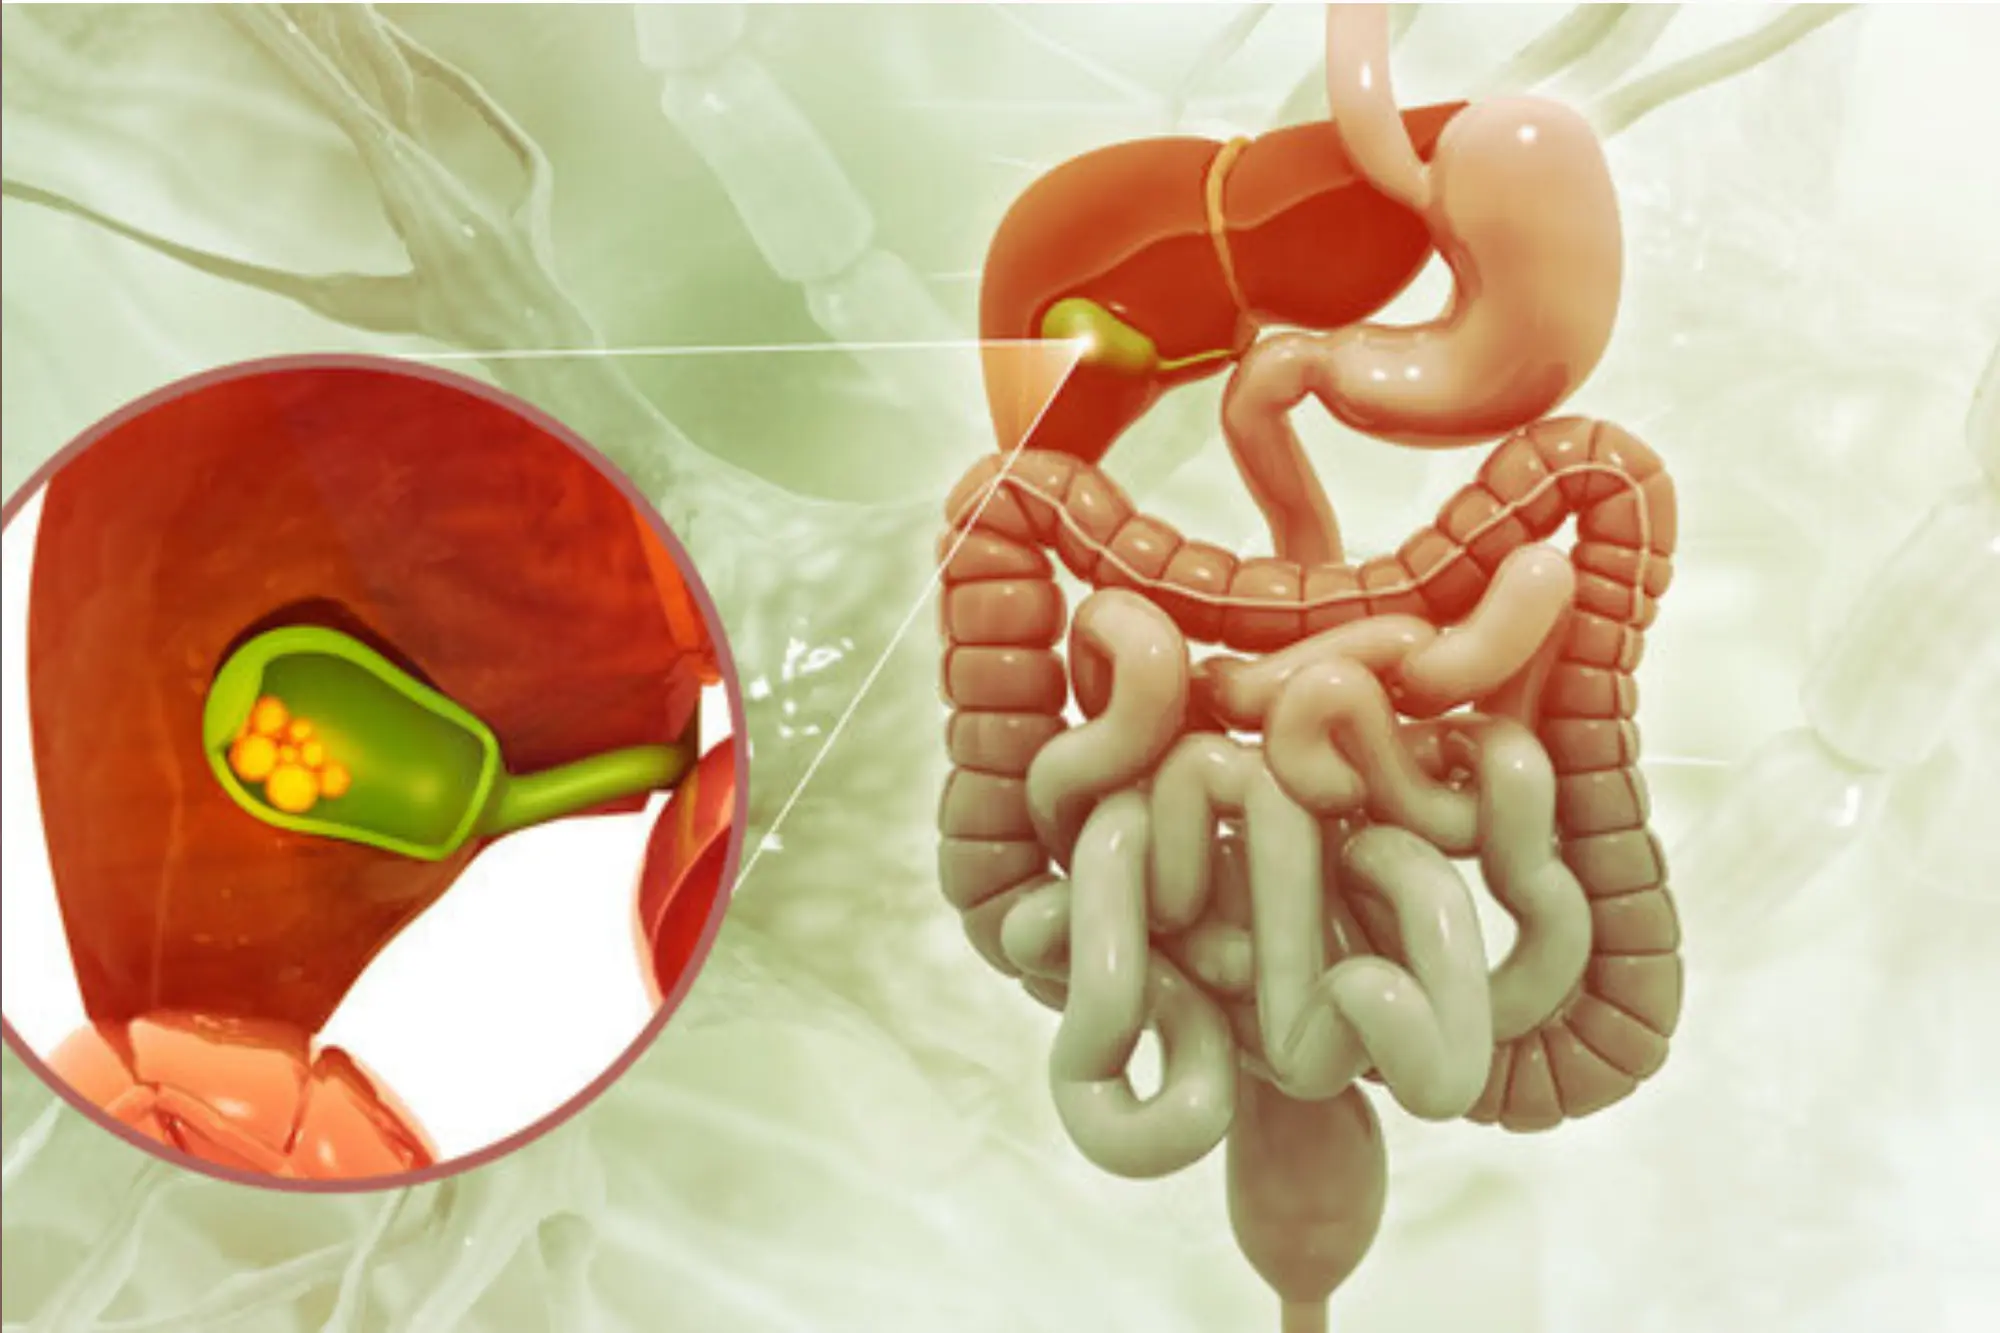

GallStone Treatment

Gallstones are hardened deposits that form in the gallbladder, often causing pain, indigestion, and other digestive issues.